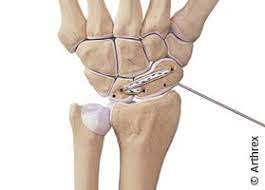

Wenn der Patient eine sitzende Tätigkeit ausübt kann er im Prinzip schon nach wenigen Tagen wieder an den Arbeitsplatz. Nach einer Handgelenk-Operation dauert die Ruhigstellung sechs bis acht Wochen. Die Schiene sollte mindestens 4 bis 6 Wochen dran bleiben.

Ein gerissenes SL-Band bedeutet für das Handgelenk einen empfindlichen Stabilitätsverlust. Wie lange die Heilung eines Bänderrisses dauert hängt von der Nachbehandlung Schonung und Wundheilung ab. Wie lange ein Bänderriss am Handgelenk bis zur vollständigen Ausheilung braucht richtet sich insbesondere nach dem Schweregrad der Verletzung.